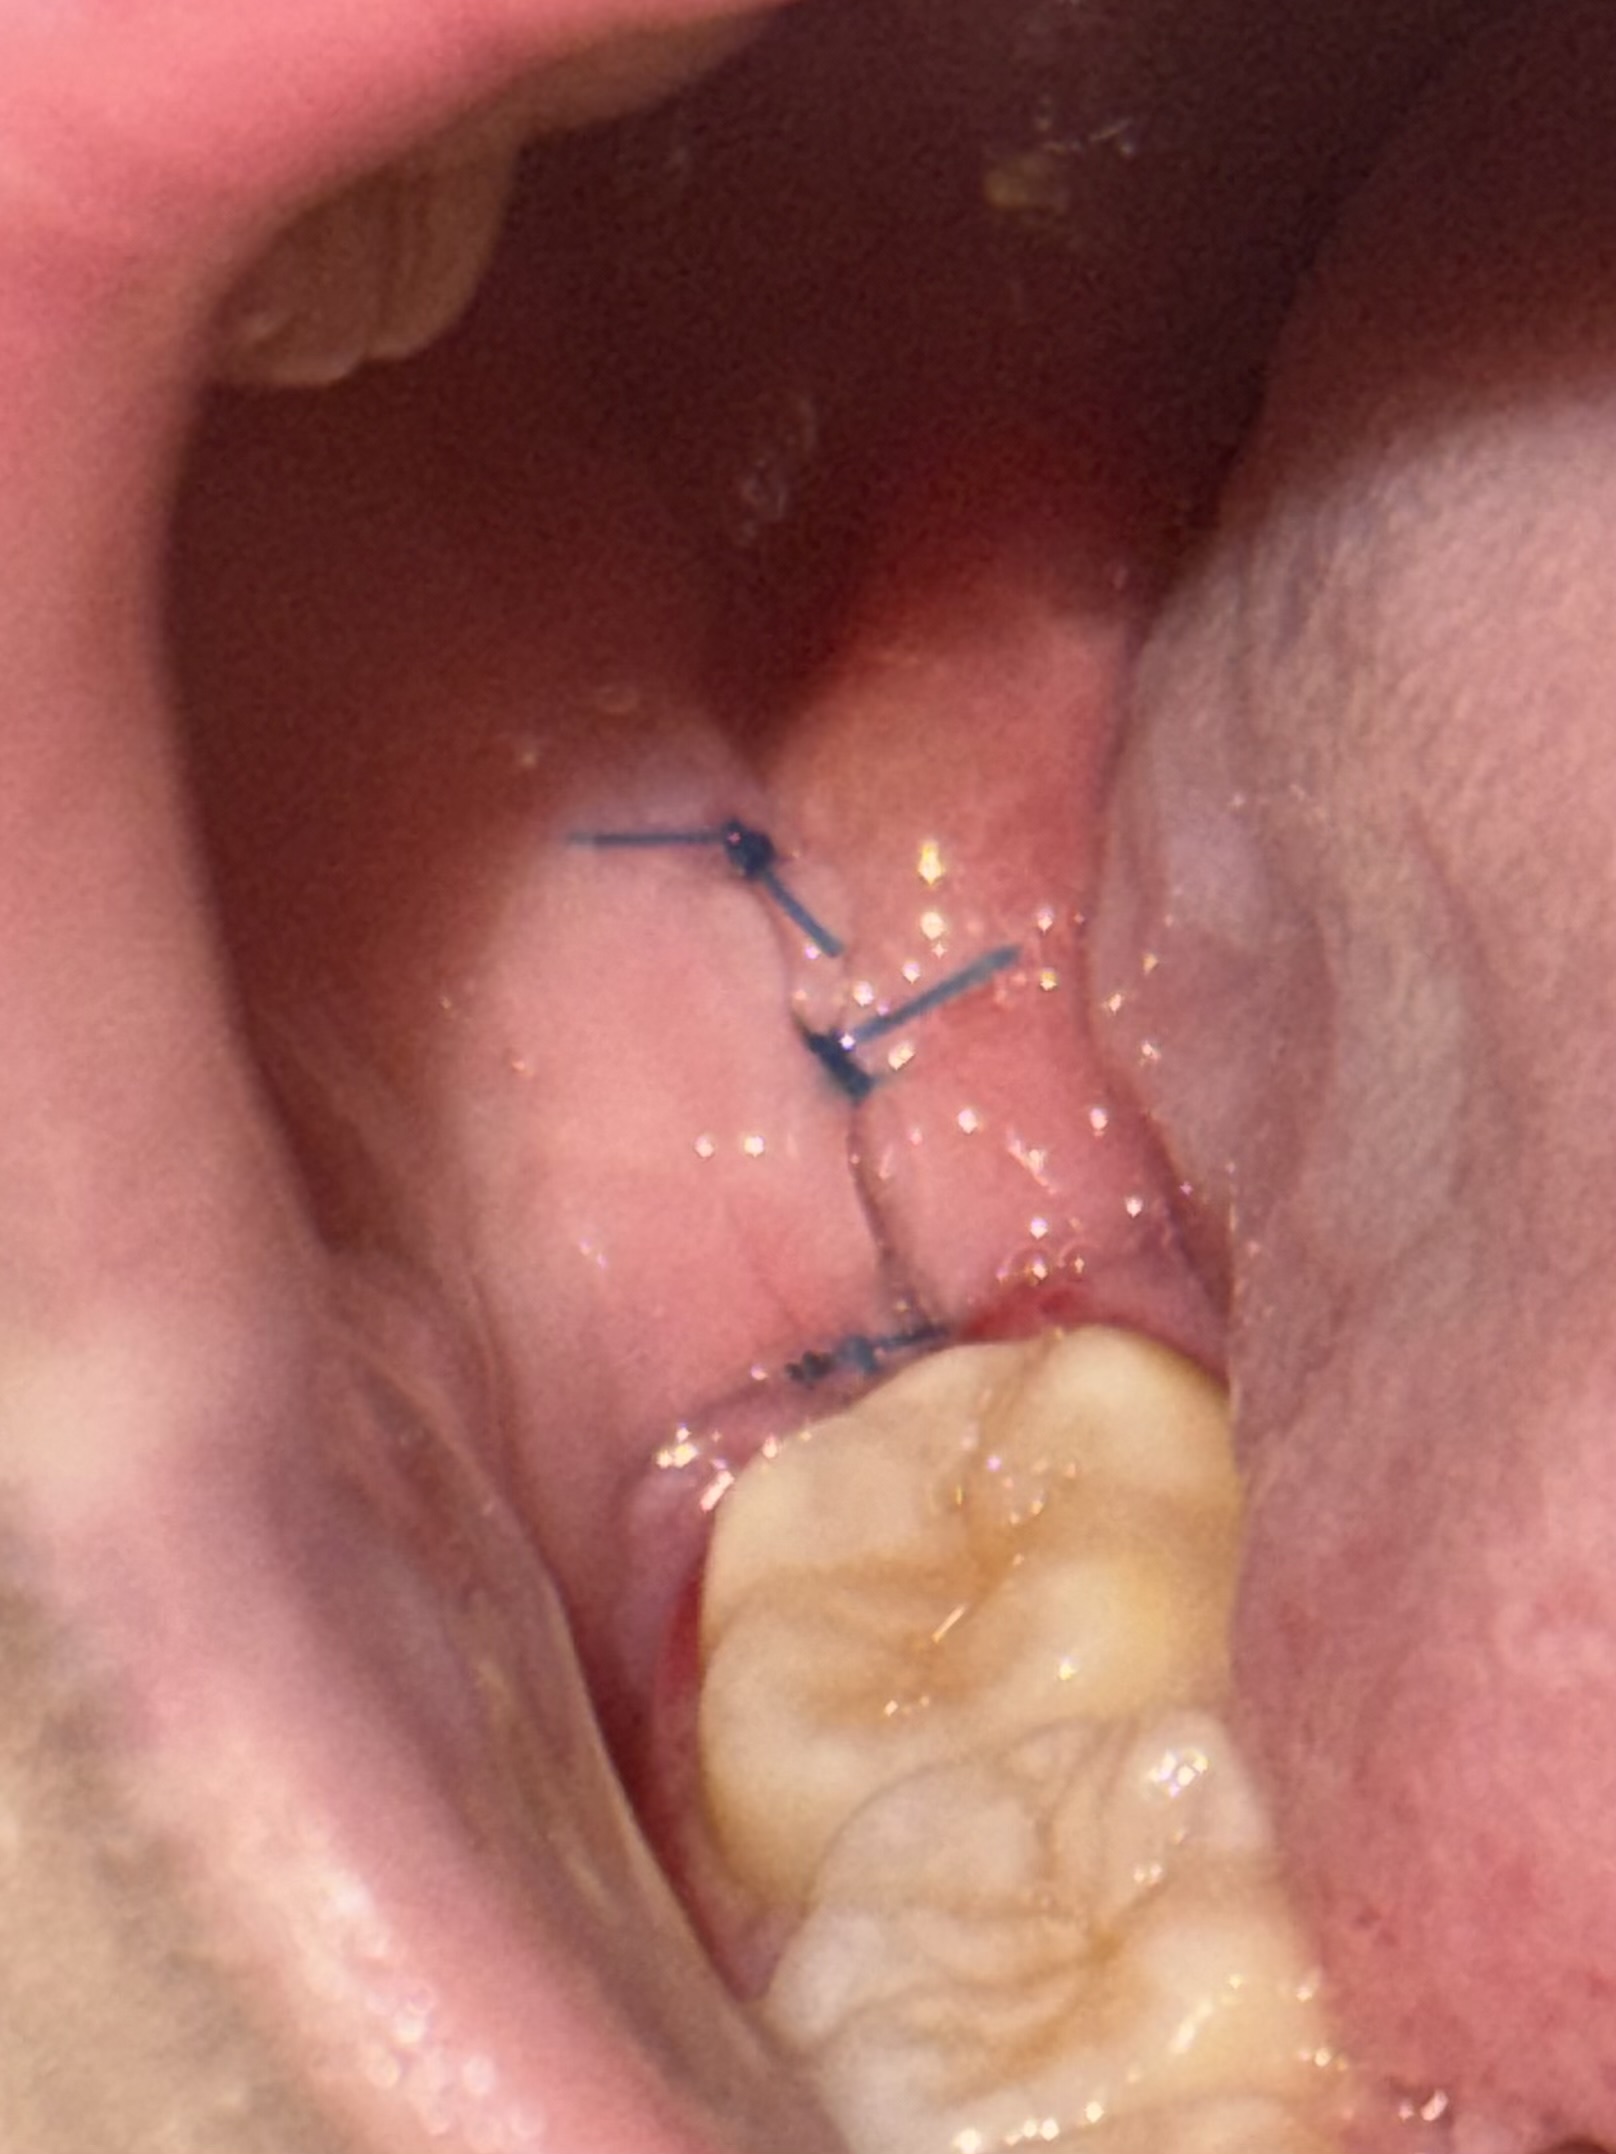

親知らず抜歯後に再掻爬をしましたが、血餅が取れてしまいました。

回答数:2 -